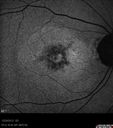

59-year-old man has macular dystrophy in both eyes. He saw Dr. Gass in 1989, at which time Dr. Gass thought it might be post inflammatory. Interestingly, at this point he still does not have a diagnosis other than macular dystrophy. His vision since he was here last is reasonably stable.

He has been diabetic for eight years. He had LASIK surgery done in 1998. He was a high myope, about a -10 and now he is about a -3. He had some vision changes in medical school in the 1980s and saw Dr. Gass for that. He had some pigment epithelial irregularities in both eyes. Dr. Gass felt maybe this was an atypical case of previous AMPPE. Otherwise he is in good health. He had strabismus as a child and had muscle surgery. He is color blind, along with many people in his family, and as far as he knows, it is congenital.

VISUAL ACUITY: Vision OD is 20/25, OS is 20/30. IOP: OD 14, OS 13. The lenses are clear.

OD: Vertical C/D ratio is 0.2. There are no vitreous cells. The retinal vessels are slightly attenuated. The retina is very thin looking.

OS: Vertical C/D ratio is 0.2. Again, the retinal vessels are attenuated. The retina does appear to be thin looking.

OCT SCAN: The OCT scan shows retinal atrophy in both eyes.

1. RETINAL ATROPHY – BOTH EYES